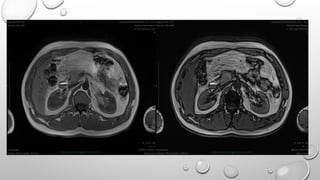

• BALANCED SSFP IS USED IN

CARDIAC IMAGING

FETAL IMAGING

ABDOMINAL IMAGING

SIEMENS : TRUE FISP

MODIFICATIONS : CISS

DESS